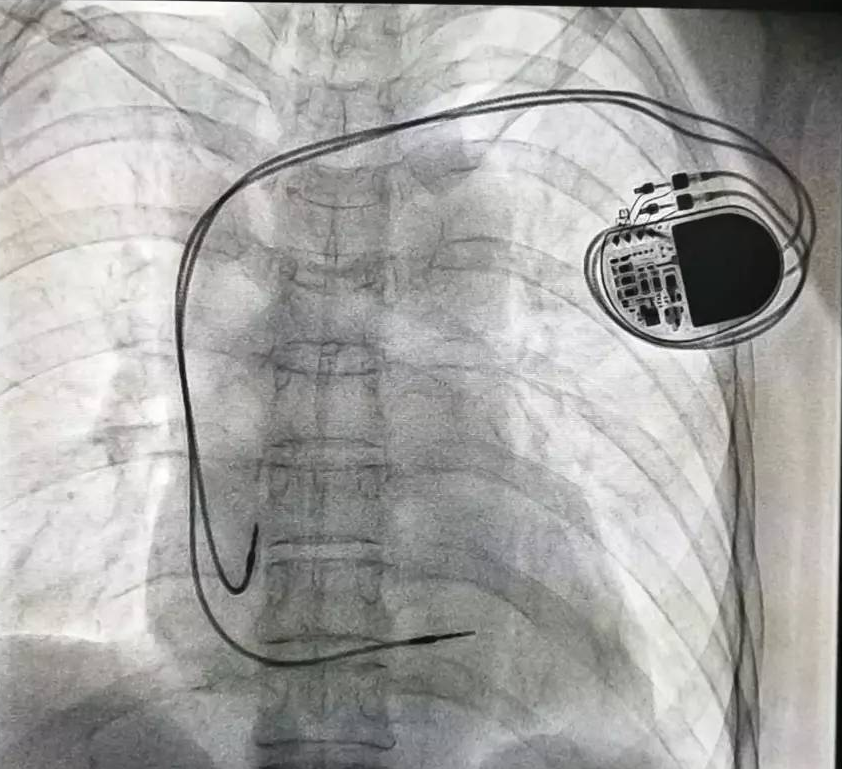

相較于傳統(tǒng)的起搏治療,Micra體積僅有維生素膠囊大小,體積比傳統(tǒng)心臟起搏器減小93%,重量僅約2克。它可通過微創(chuàng)方式植入心臟內(nèi),無導(dǎo)線、無囊袋,患者甚至感覺不到他的存在。